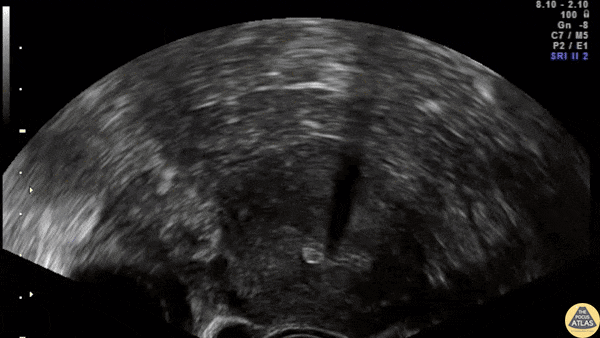

Transvaginal ultrasound showing the IUD correctly placed in both sagittal and transverse plane. Contributor: Dr. Nicolay B. Werner Akershus University Hospital, Norway